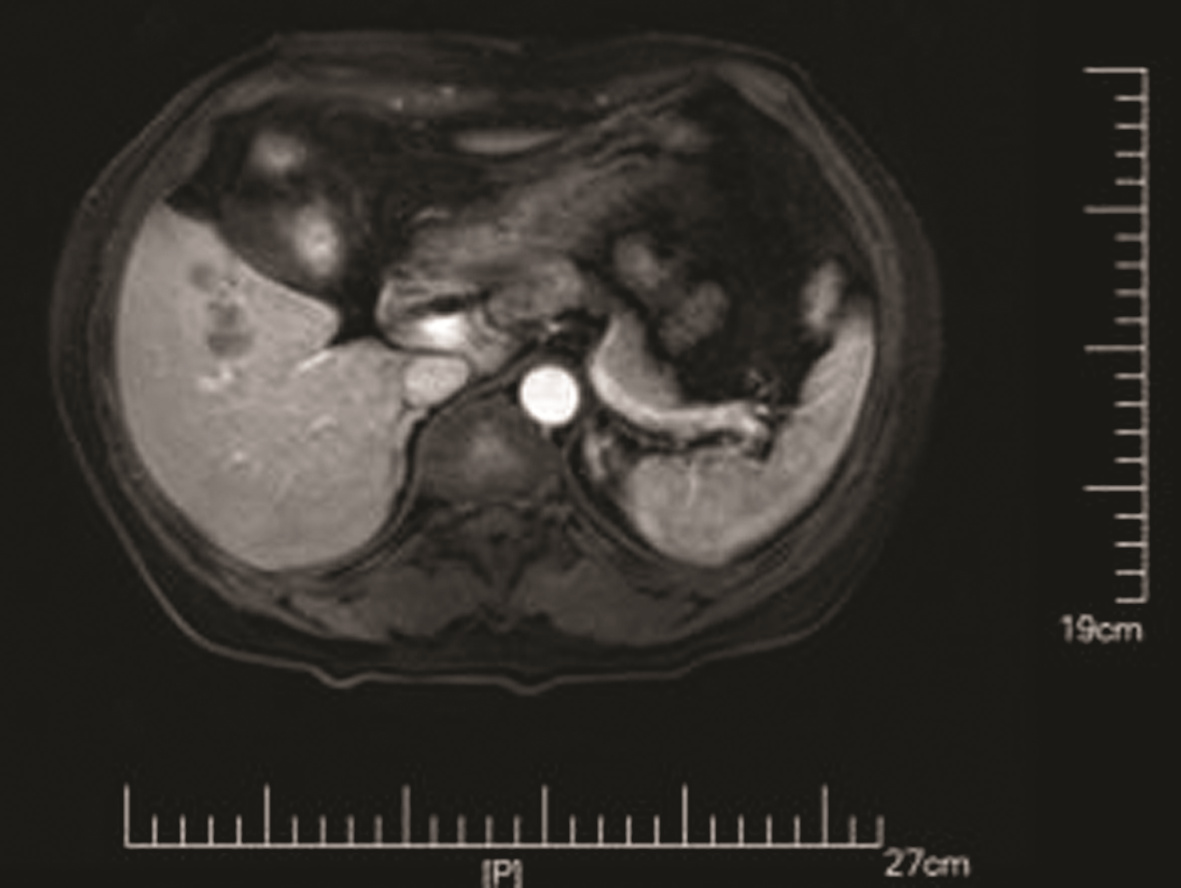

IgG4相关腹膜后纤维化1例报告

李朝霞, 刘洋, 李楠, 纪竹慧, 辛桂杰

2022, 38(5): 1126-1128. DOI: 10.3969/j.issn.1001-5256.2022.05.030

摘要(876) HTML (399) PDF (2161KB)(74)

摘要: